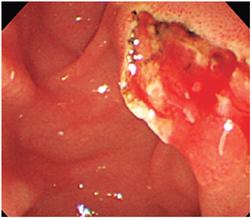

La DPBG después de una EFT limitada o pequeña fue descrita en 2003 por Ersoz y colaboradores para la remoción de cálculos >10 mm o múltiples cálculos biliares 1,8,9,12. Se utiliza para crear una mayor apertura del orificio biliar con un balón de diámetro grande (12 mm a 20 mm) para simplificar la remoción de cálculos gigantes y difíciles del conducto biliar y como una alternativa a la LM, ya que esta consume tiempo, puede generar impactación o fractura de la canastilla de Dormia y aumentar el riesgo de eventos adversos. La EFT es inicialmente recomendada como paso previo a la DPBG, ya que se cree que está asociada con una disminución del riesgo de pancreatitis pos-procedimiento (Figura 2) 8,9,13,14. Puede utilizarse como método inicial cuando se documentan cálculos gigantes en las imágenes o cuando la remoción convencional con EFT y canastilla han fallado 14,15,16.

En cuanto a las complicaciones, la tasa global de eventos adversos (pancreatitis, sangrado y perforación) es más baja para la DPBG que para la EFT sola, lo cual fue observado en 4 metaanálisis que evaluaron una comparación de DPBG más EFT con EFT sola 14,19,21,22,23. En un estudio multicéntrico de casos y controles a gran escala de 946 pacientes, el análisis de los subgrupos mostró que los cálculos mayores de 16 mm, la presencia de cirrosis y la EFT completa (grande) fueron factores independientemente asociados con la presencia de eventos adversos. Adicionalmente, la DPBG no aumenta el riesgo de pancreatitis y, en una revisión sistemática de estudios de DPBG 14, la pancreatitis ocurrió en el 2,4% de los pacientes que recibieron DPBG y EFT. Un posible mecanismo de reducción en la tasa de pancreatitis se debe a que la fuerza radial ejercida durante la dilatación con EFT se dirige hacia el conducto biliar, lejos del orificio pancreático, lo que produce una lesión periampular menor alrededor del conducto pancreático 13,14. Sin embargo, se cree que la EFT tiene un papel limitado en prevenir la pancreatitis en los pacientes con DPBG, ya que los pacientes con DPBG sin EFT no tienen un aumento en el riesgo de pancreatitis. Por esto, se ha sugerido otra hipótesis acerca del mecanismo de la pancreatitis, la que postula que la frecuencia de manipulación con canastilla de Dormia y balón de extracción -tanto en DPBG con y sin EFT- es reducida debido a que el orificio papilar es lo suficientemente amplio (Figura 5), lo que resulta en menos trauma periampular, edema y más bajo riesgo de pancreatitis, y esto explica por qué el riesgo de lesión del orificio ampular con la dilatación papilar con balones de menor calibre (<10 mm) aumenta debido al paso de los instrumentos para extracción de los cálculos por un orificio inadecuadamente ampliado 14.